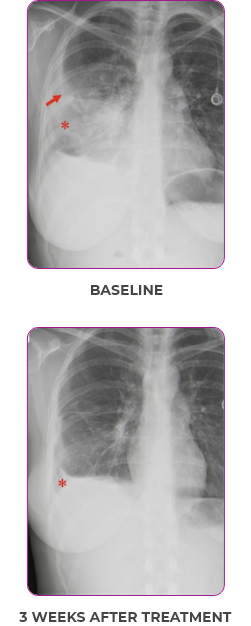

Response in primary and metastatic lesions1

Lung imaging of primary tumors.

SCAN 1: LUNG

SCAN 2: LUNG AND BONE

Response to VITRAKVI1

- Partial response and symptom improvement confirmed by chest X-rays after <1 month of treatment

- Imaging performed 6 weeks into treatment revealed considerable decrease in the size of both target lesions

- Complete clinical response achieved by 12 months with residual scarring